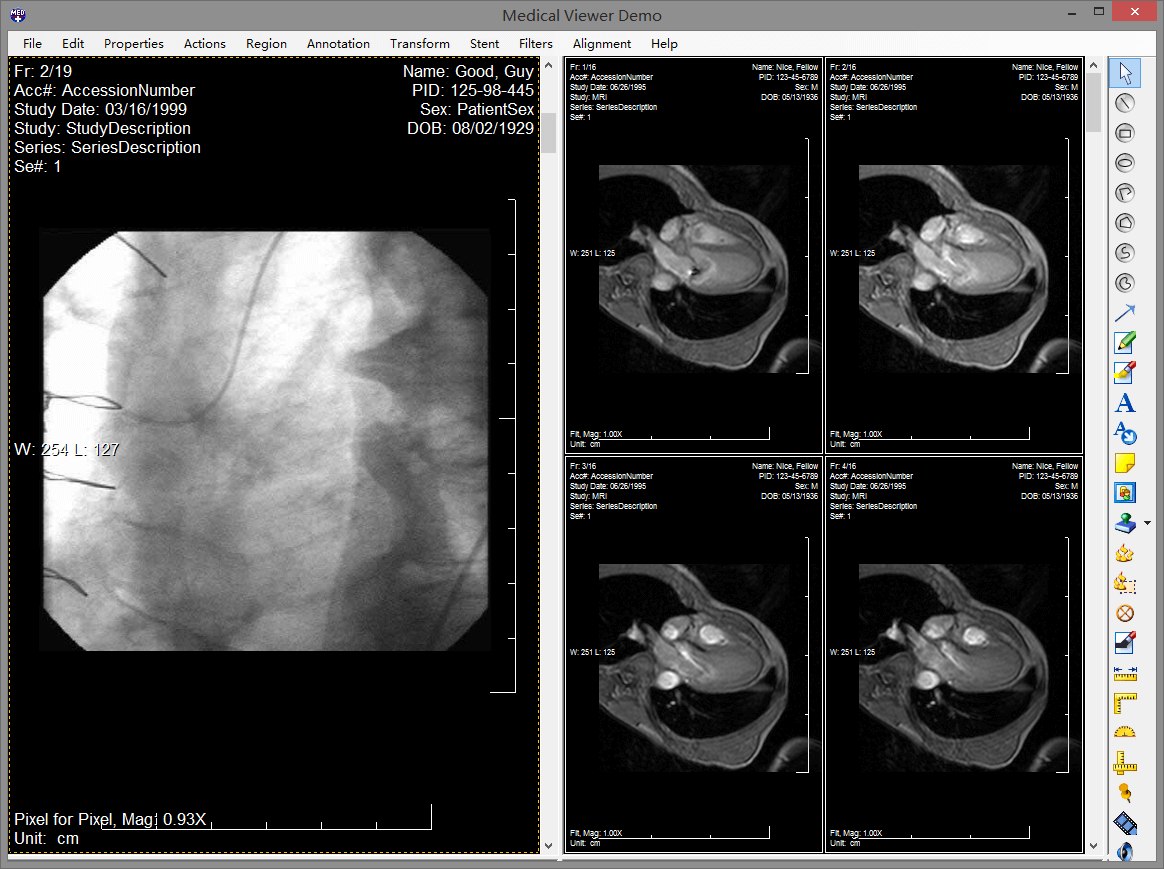

leadtools medical imaging很多年来都是世界第一的医学影像和dicom控件开发包。它提供了完整的dicom数据集、通信和安全支持、医学相关的影像处理和显示、3d重建和高级pac服务器、客户端和影像工作站的组件。同时支持hl7(health level seven卫生信息传输标准)。

使用leadtools medical imaging开发包,可以帮助医疗领域软件开发人员、医疗器械设备厂商、医院构建一个完整的pacs系统,通过成熟的开发接口和已经完成的pacs framework框架,极大的简化开发过程、节省成本,让原本复杂的技术变得简单,开发人员完全可以专注于医院业务,而不需要去研究复杂的通讯标准,因为这一切leadtools都已经帮您做好了。

leadtools pacs能够使开发人员非常容易的开发一整套完整的pacs解决方案,组建企业级pacs服务器和客户端,实现dicom通信、查询、存储dicom影像数据。leadtools拥有成熟的pacs框架,您只需要修改logo就可以轻松构建一整套pacs系统。它包含了全套的权限、服务、存储、客户端、html5 web 端,而这一切都是基于多年大型医院需求的总结体现,并且已经完整的在超过150家医院真正部署。

leadtools 能够使您快速创建高质量、全功能和安全的基于web的医学影像工作站,您可以在上面查看3d图像、标注、测量、灰度等等。完全不需要部署任何的客户端,实现零空间占用。这样您就可以轻松的在iphone、ipad、android和windows phone上随时随地查看病人信息。一次开发,跨平台使用,您再也不必头疼需要为医院开发不同客户端了,只需要html5 web端就可以全平台浏览器支持。

leadtools为开发者提供了一套非常全面的示例代码库,它被包含在安装包中,开发者可以非常简单的部署、运行,学习leadtools的所有功能。其中包含整套pacs服务器和客户端源代码。